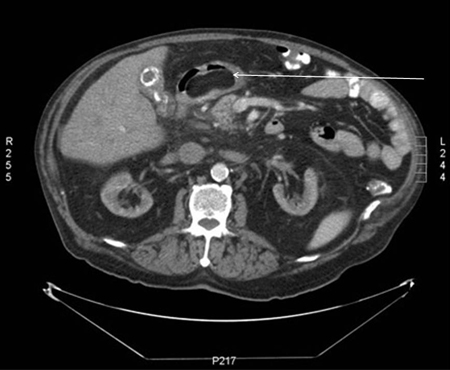

[Figure caption and citation for the preceding image starts]: Gastric submucosal lipoma, CT scan. Submucosal antral mass with fatty density throughout.From the collection of Dr Kimberly Moore Dalal and Dr Steven D. DeMartini; used with permission [Citation ends].